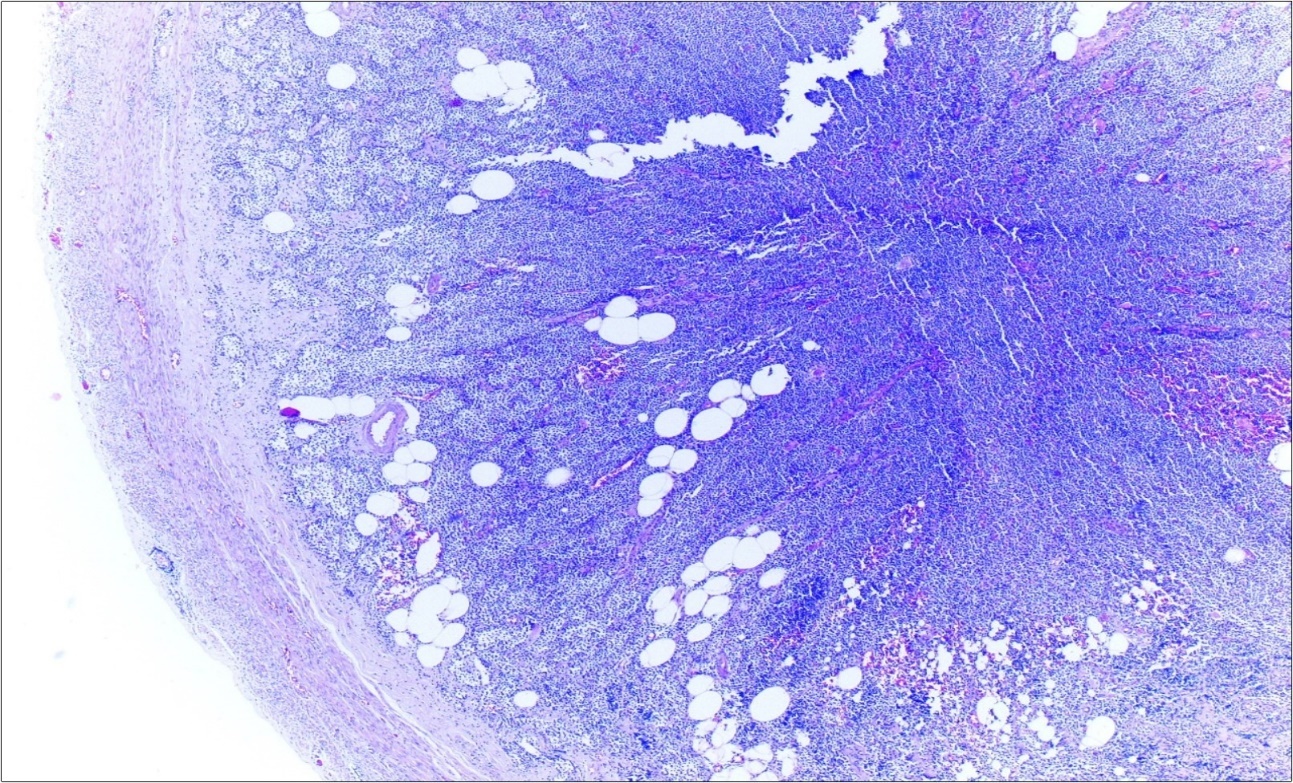

A 63-year-old woman presented to the Department of General Surgery as an outpatient with abdominal pain. Physical examination showed the signs of acute appendicitis and appendectomy was performed. During microscopic examination, a small focus of atypical monotonous lymphoid cell population was seen and the material was sampled totally. The pathological examination revealed MALT lymphoma (Figure 1), with diffuse positivity of cluster of differentiation (CD) 20 (Figure 2), CD 79a and B-cell lymphoma (Bcl- 2) (Figure 3) with just a few CD3 positive lymphoid cells. However, no evidence of adenocarcinoma was found in the appendectomy specimen. After the diagnosis of lymphoma, a complete colonoscopy was planned and this revealed a solid tumoral mass in the caecum measuring 5x4x4 cm. Computed tomography of the abdomen and pelvis revealed mesenteric lymphadenopathy associated with a mass in the caecum with multiple nodules in liver consistent with metastasis (Figure 4). Frozen sections were not obtained since the treatment method would not be affected. The patient underwent anterior resection with regional lymphadenectomy, with the pathological assessment of the resected specimen revealing a collision tumor consisting of a poorly differentiated adenocarcinoma extending through the muscularis propria with MALT lymphoma (Figure 5). Microscopic evaluation of the 11 regional lymph nodes in the mesentery of the resected colon and liver biopsy showed diffuse infiltration of MALT lymphoma with metastasis of adenocarcinoma (Figure 6). According to immunohistochemistry, atypical lymphocytes were positive for CD 20, Bcl-2, and negative for CD3, CD5, CD10, CD23, Bcl-6, terminal deoxynucleotidyl transferase, and cyclin D1. The proliferation fraction (MIB-1 immunostaining) was approximately 20%. The morphological and immunohistochemical findings were used to confirm the diagnosis of synchronous presentation of MALT lymphoma and colon adenocarcinoma within the caecum, mesenteric lymph nodes and liver metastases.

Figure 1.Appendix lumen infiltrated with B lymphoid cells (h&e;x100)

Appendix lumen infiltrated with B lymphoid cells (h&e;x100)